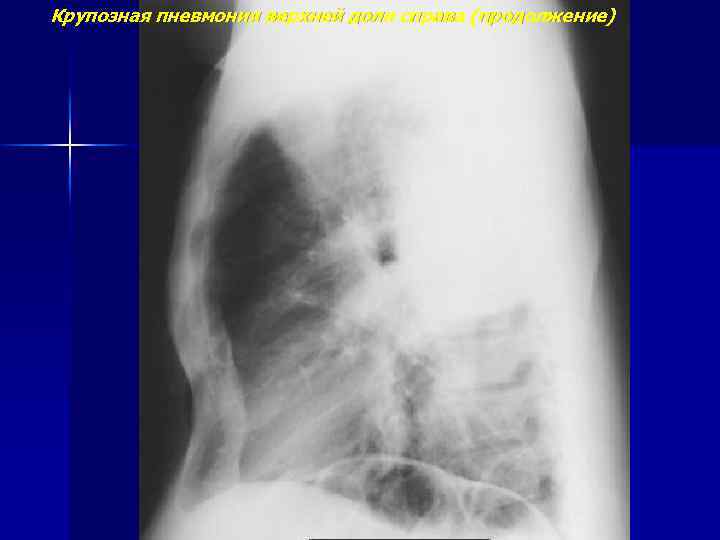

Крупозная пневмония верхней доли справа

Крупозная пневмония верхней доли справа (продолжение)